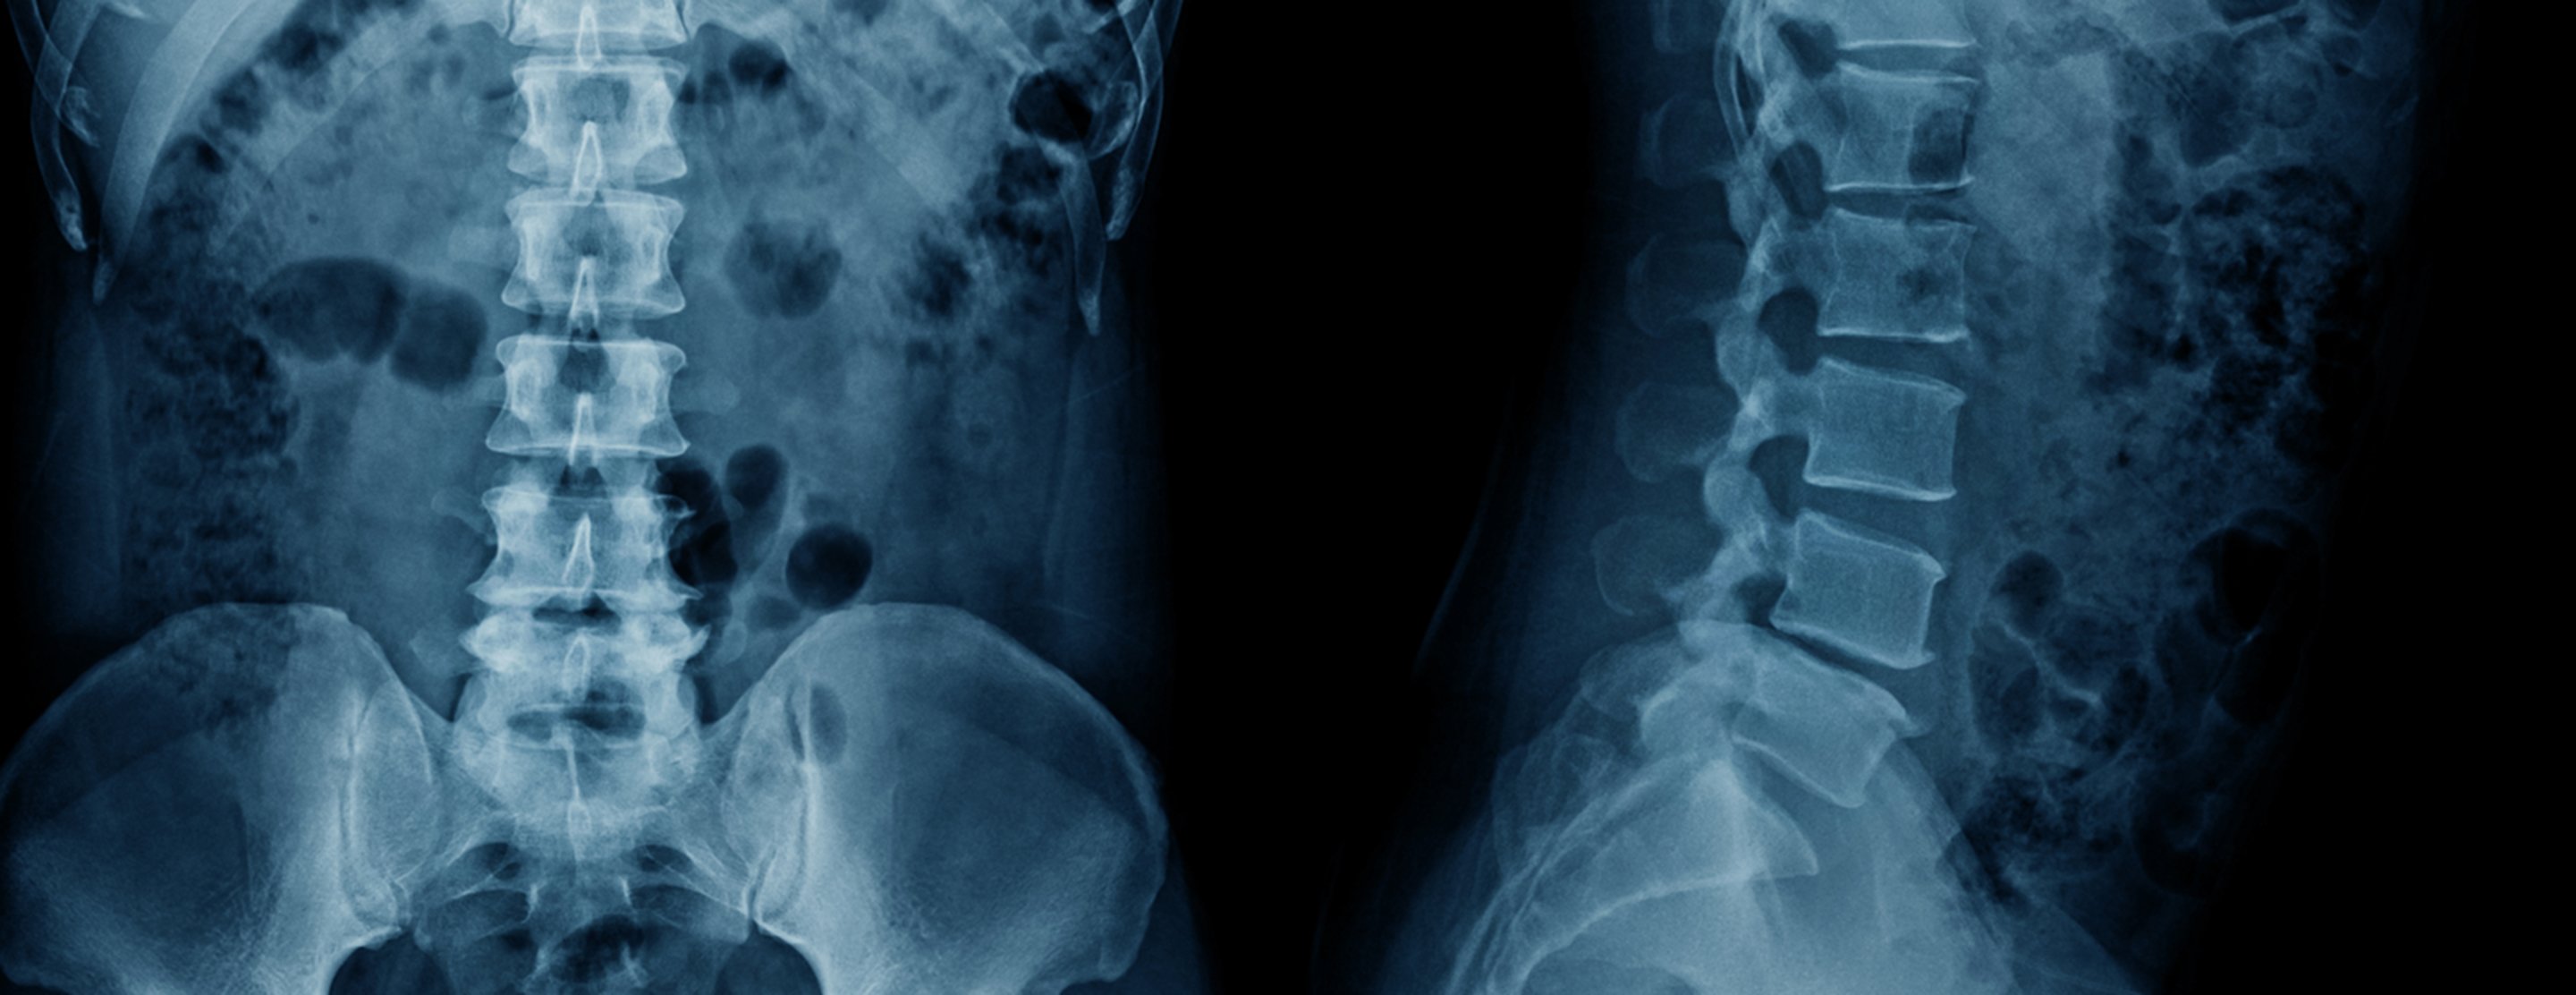

Disk replacement - lumbar spine

Lumbar spine disk replacement is surgery of the lower back (lumbar) area. It is done to treat spinal stenosis or disk problems and allow normal movement of the backbone.

During total disk replacement (TDR), the inner portion of a damaged spinal disk is replaced with an artificial disk to restore normal movement of the backbone.

Your provider will order an imaging test such as an MRI, CT scan, or x-ray to check if you need surgery.